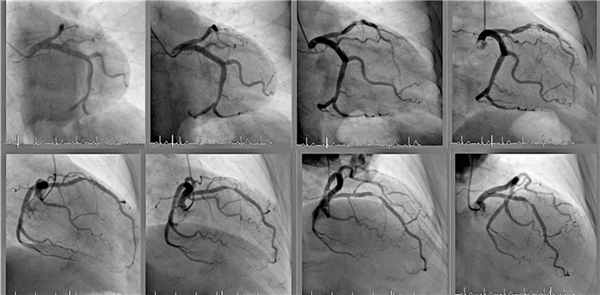

Рис.1. Острый тромбоз правой коронарной артерии. Больной С. 68 лет, лиагноз: ОКС с полъемом ST, провелена ТЛБАП, восстановлен кровоток TIMI - III.

Рис.2. Острый тромбоз перелней межжелулочковой артерии. Больной Б., 34 гола, лиагноз: ОКС с полъемом ST, провелено стентирование коронарной артерии, восстановлен кровоток TIMI - III.